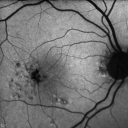

76-year-old woman has juxtafoveal retinal telangiectasis. She had Stage five neovascularization in the left eye I treated with injections between September of 2007 and October of 2008 with Avastin (3 years ago). Since then she has not had a recurrence. Her vision remains good. The left eye is her better eye. She does notice the distance vision declining slightly.

VISUAL ACUITY: OD 20/400, OS 20/40. IOP: 10 OU. The posterior chamber intraocular lens is in good position in both eyes.

OD: Vertical C/D ratio is 0.1. There is hyperpigmentation temporal to the fovea.

OS: Vertical C/D ratio is 0.1. There is hyperpigmentation temporal to the fovea. Photos confirm clinical findings.

FLUORESCEIN ANGIOGRAPHY: Fluorescein angiography shows diffuse hyperfluorescence in an annular fashion around the macula in each eye with hypofluorescence corresponding to the pigment spots.

FUNDUS AUTO FLUORESCENCE: Shows hypofluorescence corresponding to the pigment spots.

SPECTRALIS-SD-OCT SCAN: The OCT scan shows typical intraretinal cysts in each eye, but there is no evidence of any increased retinal thickness in either eye and there is no evidence of any recurrent neovascularization in the right eye. The right eye does have a true full thickness macular hole.